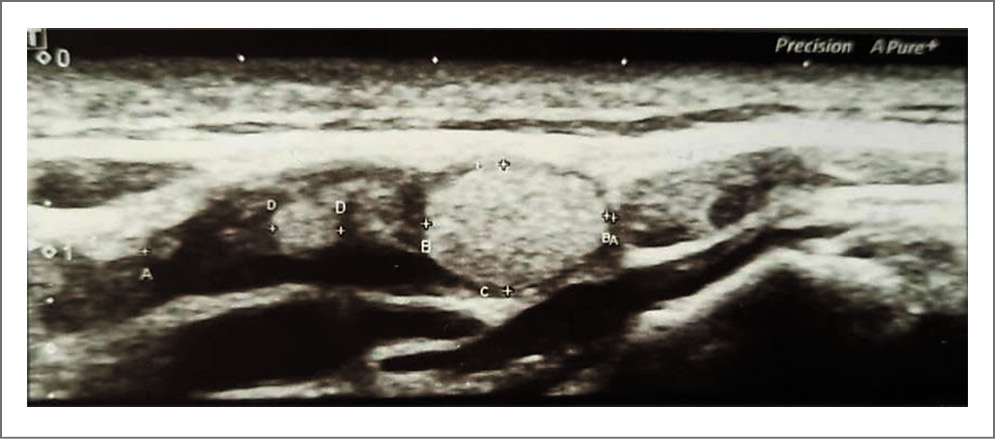

Выполнено ультразвуковое исследование периферических лимфоузлов 08.10.2021; картина представлена на рис. 5–8.

Рис. 7. Патологический очаг: в правой поднижнечелюстной области медиальнее правой поднижнечелюстной слюнной железы лоцируется гипоэхогенное образование размером 23,8×22,3×20 мм неправильной формы с неровным четким контуром, с неоднородной структурой за счет чередования участков средней и низкой эхогенности. В режиме центрального дуплексного картирования кровоток в патологическом очаге не определяется. За задней стенкой отмечается усиление эхосигнала, определяются боковые акустические тени. На границе поднижнечелюстной железы и патологического очага в паренхиме железы лоцируется расширенный до 5 мм выводной проток.